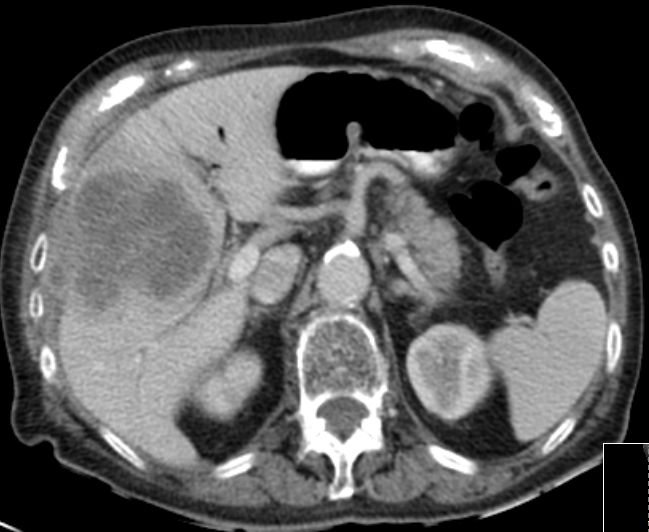

89-jährige Frau mit Infektzeichen. Zunächst sonographisch Verdacht auf Gallenblasenempyem. Im CT ein Gallenblasenkarzinom mit Leberinfiltration. Wegen Alter und AZ palliative Versorgung. | ||